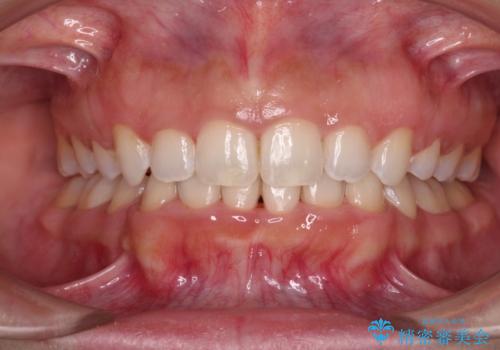

- 下顎の前突感と前歯の叢生を気にして来院された患者様です。

下顎前方位の骨格のため、下顎歯列に対して上顎歯列の幅が狭くなっていました。

急速拡大装置を用いて上顎骨を側方に拡大し、上顎の叢生を解消するとともに下顎歯列拡大により下顎の叢生も解消することとしました。

急速拡大装置使用直後は著しいスペースが正中に発現するため、ワイヤー矯正を行いますが、今回は治療期間を短くしたいとのことで、上下全体をワイヤー装置にて矯正治療することとしました。